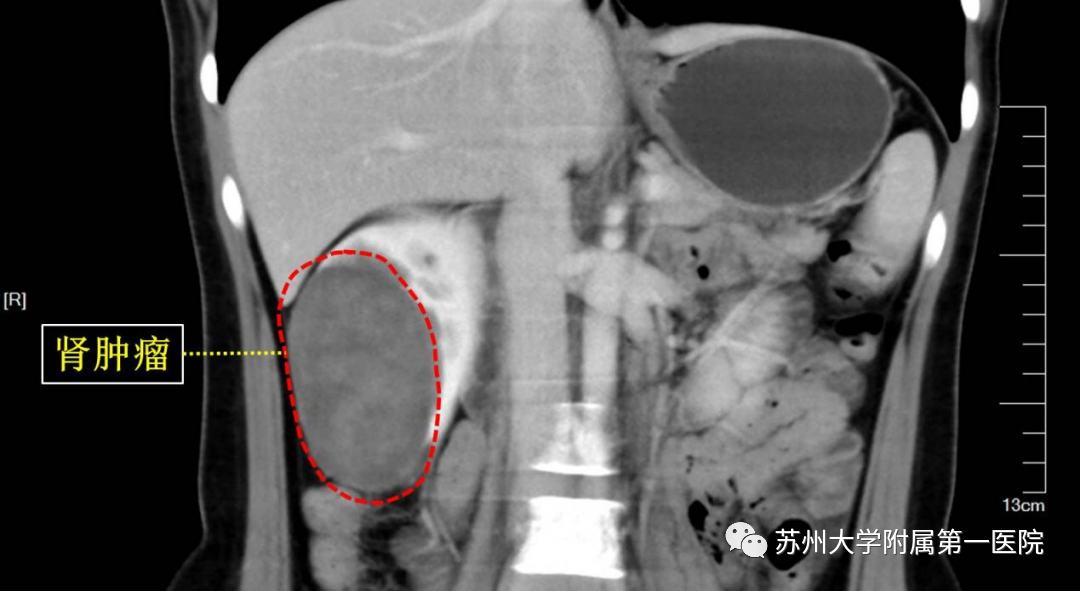

三十岁姑娘小张,家庭事业双丰收,偶然体检发现右肾9厘米的肿瘤,性质不明,一家人如晴天霹雳,先后辗转多家医院就诊,均建议做一侧根治性肾切除。 要切掉一个肾脏,对长远的角度上看,肯定会影响到患者的生活质量,小张一家人有些犹豫。 后来,小张慕名来到苏大附一院,找到泌尿外科周峰主任,周峰主任仔细阅片,量身定制治疗方案,小张肾脏约11厘米大小,但肿瘤有9厘米! 相对来说肿瘤实在太大了,根治性切除术固然是最保守的治疗方案。 但患者非常年轻,手术治疗彻底的情况下考虑长久恢复,还是可以尝试微创行腹腔镜保留肾单位的肾部分切除术,保留剩余的肾脏,保全患者肾功能。 最后经过和患者及家属的充分沟通和积极术前准备后,在科室主任黄玉华教授、平季根教授的支持下,周峰主任所在的肿瘤微创团队为小张做了腹腔镜微创保肾手术,手术过程顺利,完整切除了肿瘤,保下了半个肾脏,结果皆大欢喜。 术后及四月份复查结果:保留的部分肾脏功能完好,能够继续为小张的健康贡献一份力。 据全国肿瘤防治研究办公室和卫生部卫生统计信息中心统计,我国肾癌发病率呈逐年上升趋势,大多数肾癌患者是由于健康查体时发现的无症状肾癌。 对局限性或局部进展性(早期或中期)肾癌患者采用以外科手术为主的治疗方式。外科手术治疗肾癌通常是首选治疗方法,也是目前被公认可治愈肾癌的手段。 对早期肾癌患者可采用保留肾单位手术(保留肾脏的手术)或根治性肾切除术。这些手术可以采用腹腔镜手术或传统的开放性手术进行。Ⅰ、Ⅱ期肾癌患者治疗后5年生存率分别可达到92%、86%。 周峰主任所在的泌尿外科肿瘤治疗团队,发起了“肾脏保卫战”之“千肾计划”,大力推行微创保肾手术。 对于早、中期肾癌,机器人或腹腔镜微创行保留肾单位的肾肿瘤切除术,有效治疗肿瘤的同时,全力保护患者肾功能,保障患者的长期健康和生活质量。 苏大附一院泌尿外科肿瘤治疗团队 始终以保护患者肾功能为宗旨, 必将为广大早中期肾肿瘤患者带来更多收益, 着力提高患者生活质量。